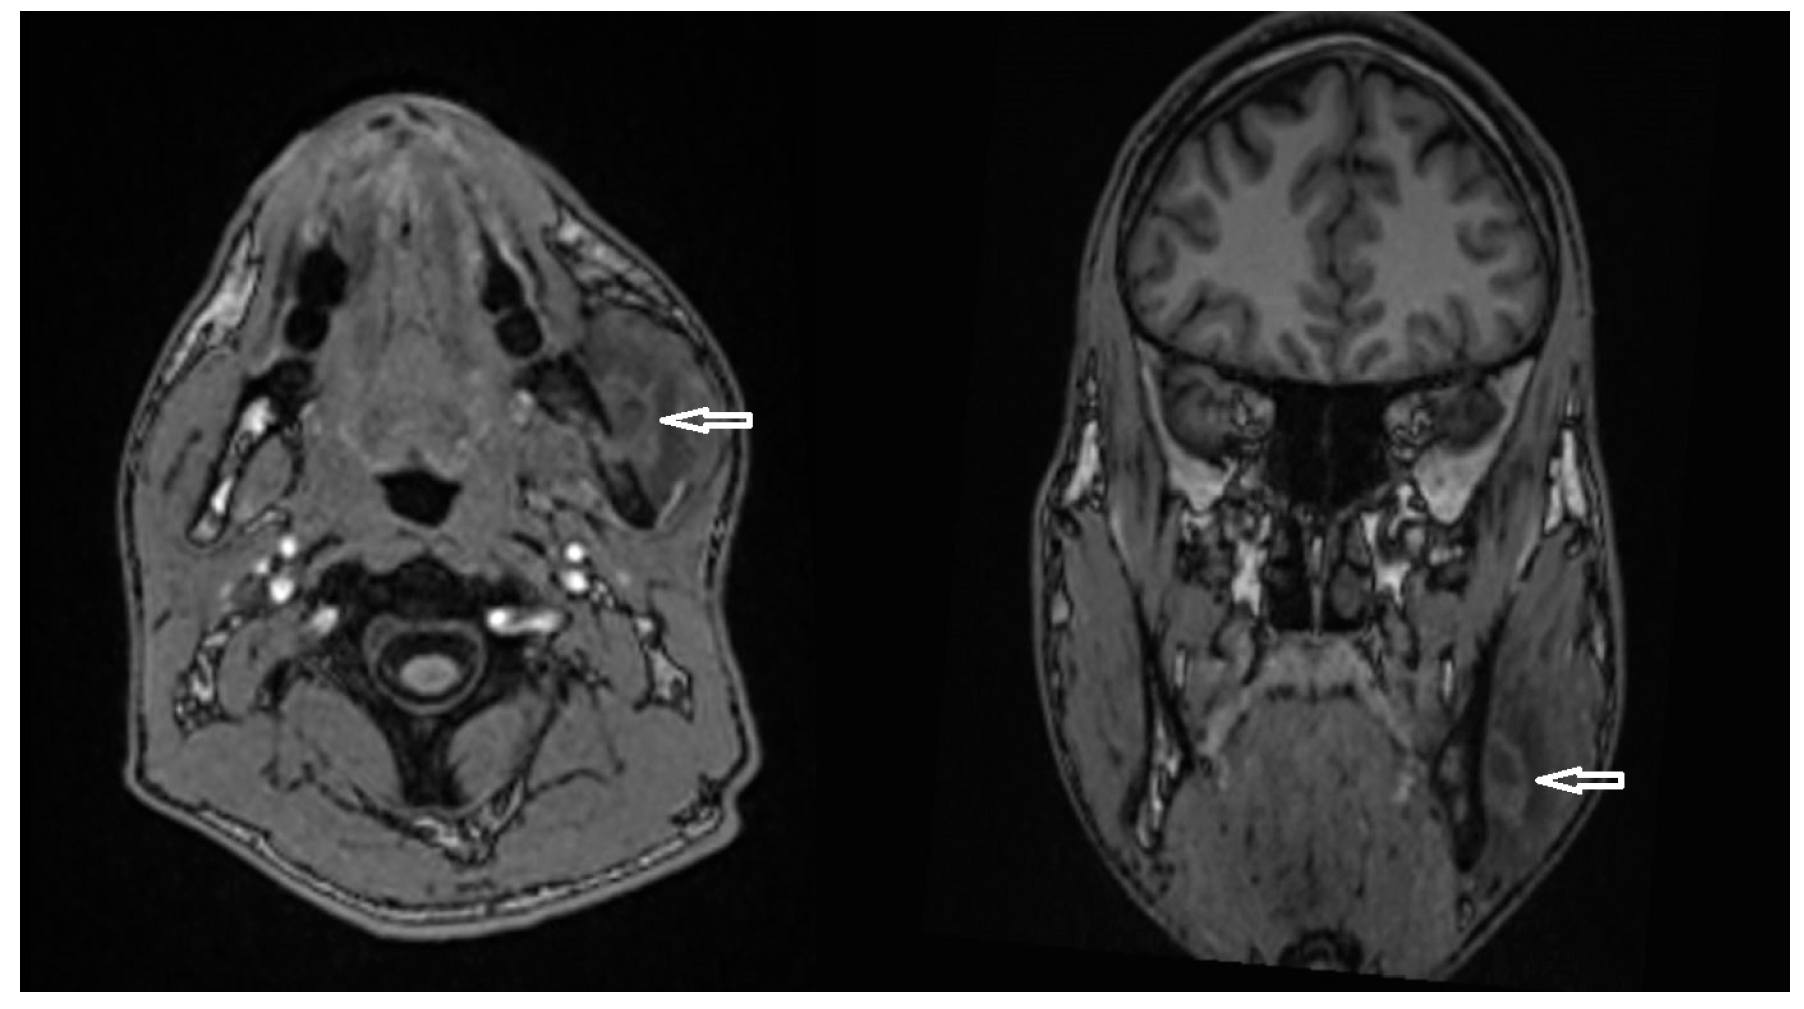

- Case 4

- Case 5